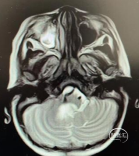

术前头部MRI

右侧桥小脑角区可见一不规则等T1、等-T2信号灶,大小约46*51*55mm3边界欠清,病灶突入四脑室内,第四脑室受压变窄,强化明显。